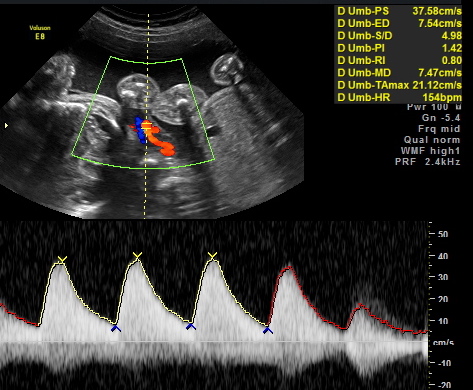

All of their organs (kidneys, bladders, hearts, brains, stomachs) look great and are also appropriate sizes. The blood flow to Elle has improved and has stabilized. All heart rates remain within normal limits, and are often on the higher side, which is probably because they just can’t sit still. We are truly excited to meet our little wiggle worms!